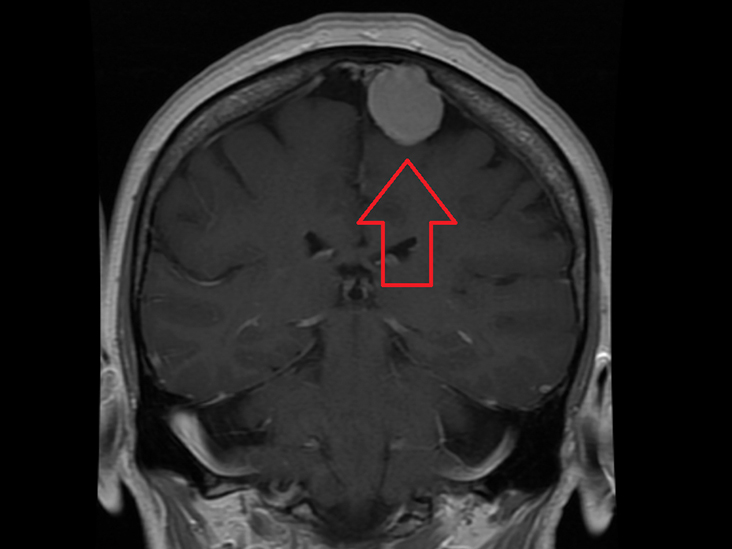

MRI檢查所獲得的圖像清晰、精細(xì)、分辨率高,對比度好,信息量大,能更客觀更具體地顯示人體內(nèi)的解剖組織及相鄰關(guān)系,對病灶能更好地進(jìn)行定位定性,并以其多參數(shù)、多序列、多方位和組織分辨率高等特點(diǎn)及能行MR水成像、MRI功能成像和MRI波譜檢查等獨(dú)特優(yōu)勢廣泛用于中樞神經(jīng)系統(tǒng)、頭頸部和軟組織病變的診斷,尤其對早期腫瘤的診斷有很大的價(jià)值。

與常規(guī) X 射線和 CT 相比,MRI 可以更清楚地看到大腦、脊髓和神經(jīng),以及肌肉、韌帶和肌腱;出于此因,MRI 常用于對膝蓋和肩部損傷進(jìn)行成像。

在大腦中,MRI 可以區(qū)分白質(zhì)和灰質(zhì),也可用于診斷動脈瘤和腫瘤。由于 MRI 不使用 X 射線或其他輻射,因此當(dāng)診斷或治療需要頻繁成像時(shí),尤其是在大腦中,它是優(yōu)選的成像方式。然而,MRI 比 X 射線成像或 CT 掃描更昂貴。